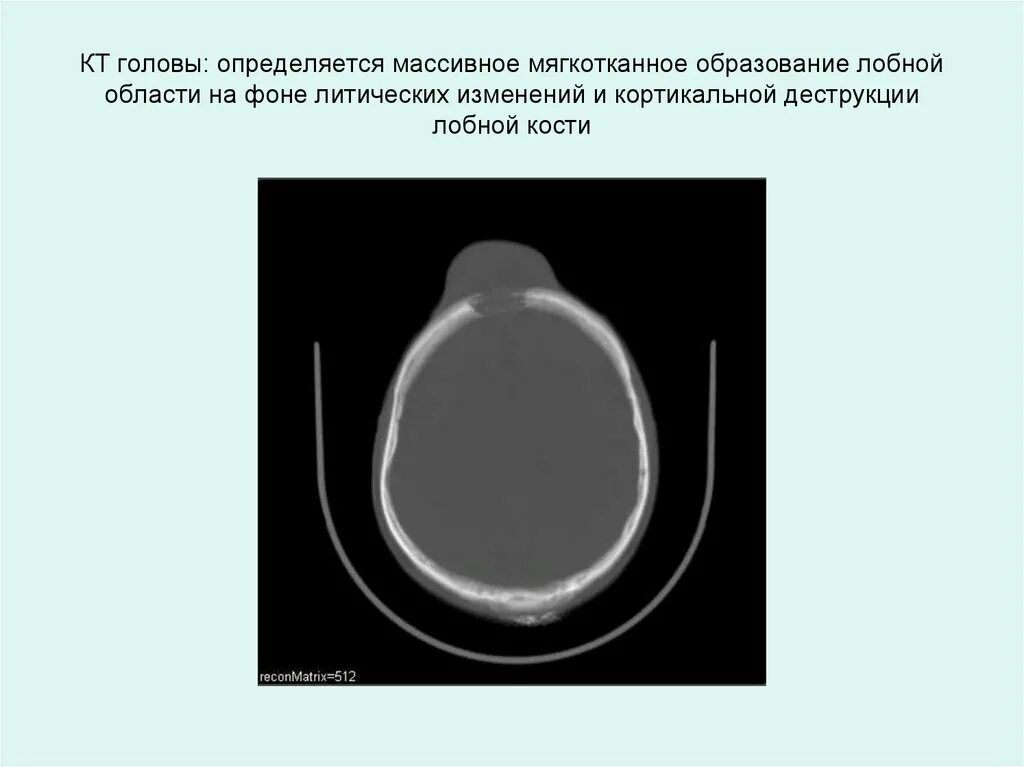

Образование мягких